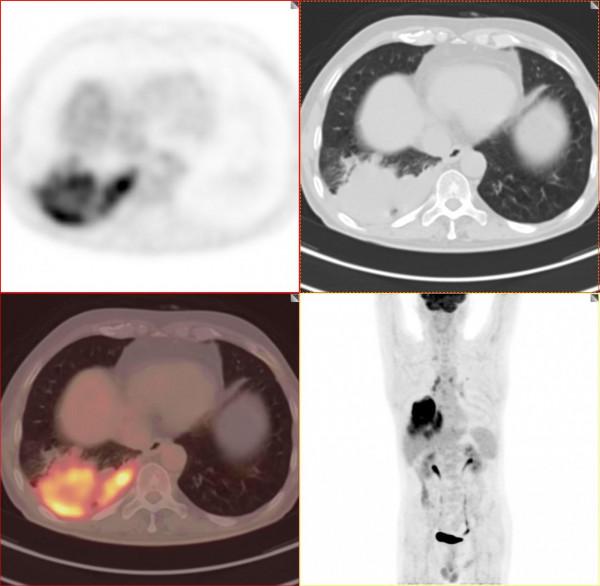

今天和大家分享的是一位晚期肺癌的患者,2021年8月份來接診。男性 67歲老人,由於平時不注重體檢,發現咳嗽伴痰中帶血才來就診,CT發現肺內佔位,腫瘤指標多項升高。發現時病灶最大徑已經超過8cm,病灶累及相鄰胸膜,腫瘤T分期達到T4期,相鄰胸膜受到明顯累及,M分期達到M1a,淋巴結轉移未知,一起來看看這個巨大的腫塊。

這個腫塊CT診斷診斷不難,能明確是肺癌,但下一步處理必須進行腫瘤分期。一定要明確全身情況,進行腫瘤分期。透過第一次PET/CT檢查的影象,我們做一個腫瘤分期,看看這個病變有沒有轉移。肺癌包括其他惡性腫瘤治療,第一步就是進行腫瘤分期。

我們看著一團"火"一樣的病灶就是這個肺癌,由於腫瘤生長速度快,血供跟不上,中心出現液化壞死區,中央出現一個“窟窿”。

上面兩張圖提示病灶累及胸膜胸腔出現少量積液。非常幸運的是該患者沒有出現明顯的區域淋巴結轉移及遠處轉移。由於病灶太大,相鄰胸膜受到累及。依據NCCN、AJCC最新指南我們進行腫瘤分期。

T分期:T4

N分期:N0

M分期:M1a

綜合分期:Ⅳa期

四期肺癌指南不建議手術,為了後續治療,患者進行了病理活檢。

病理結果:低分化鱗癌